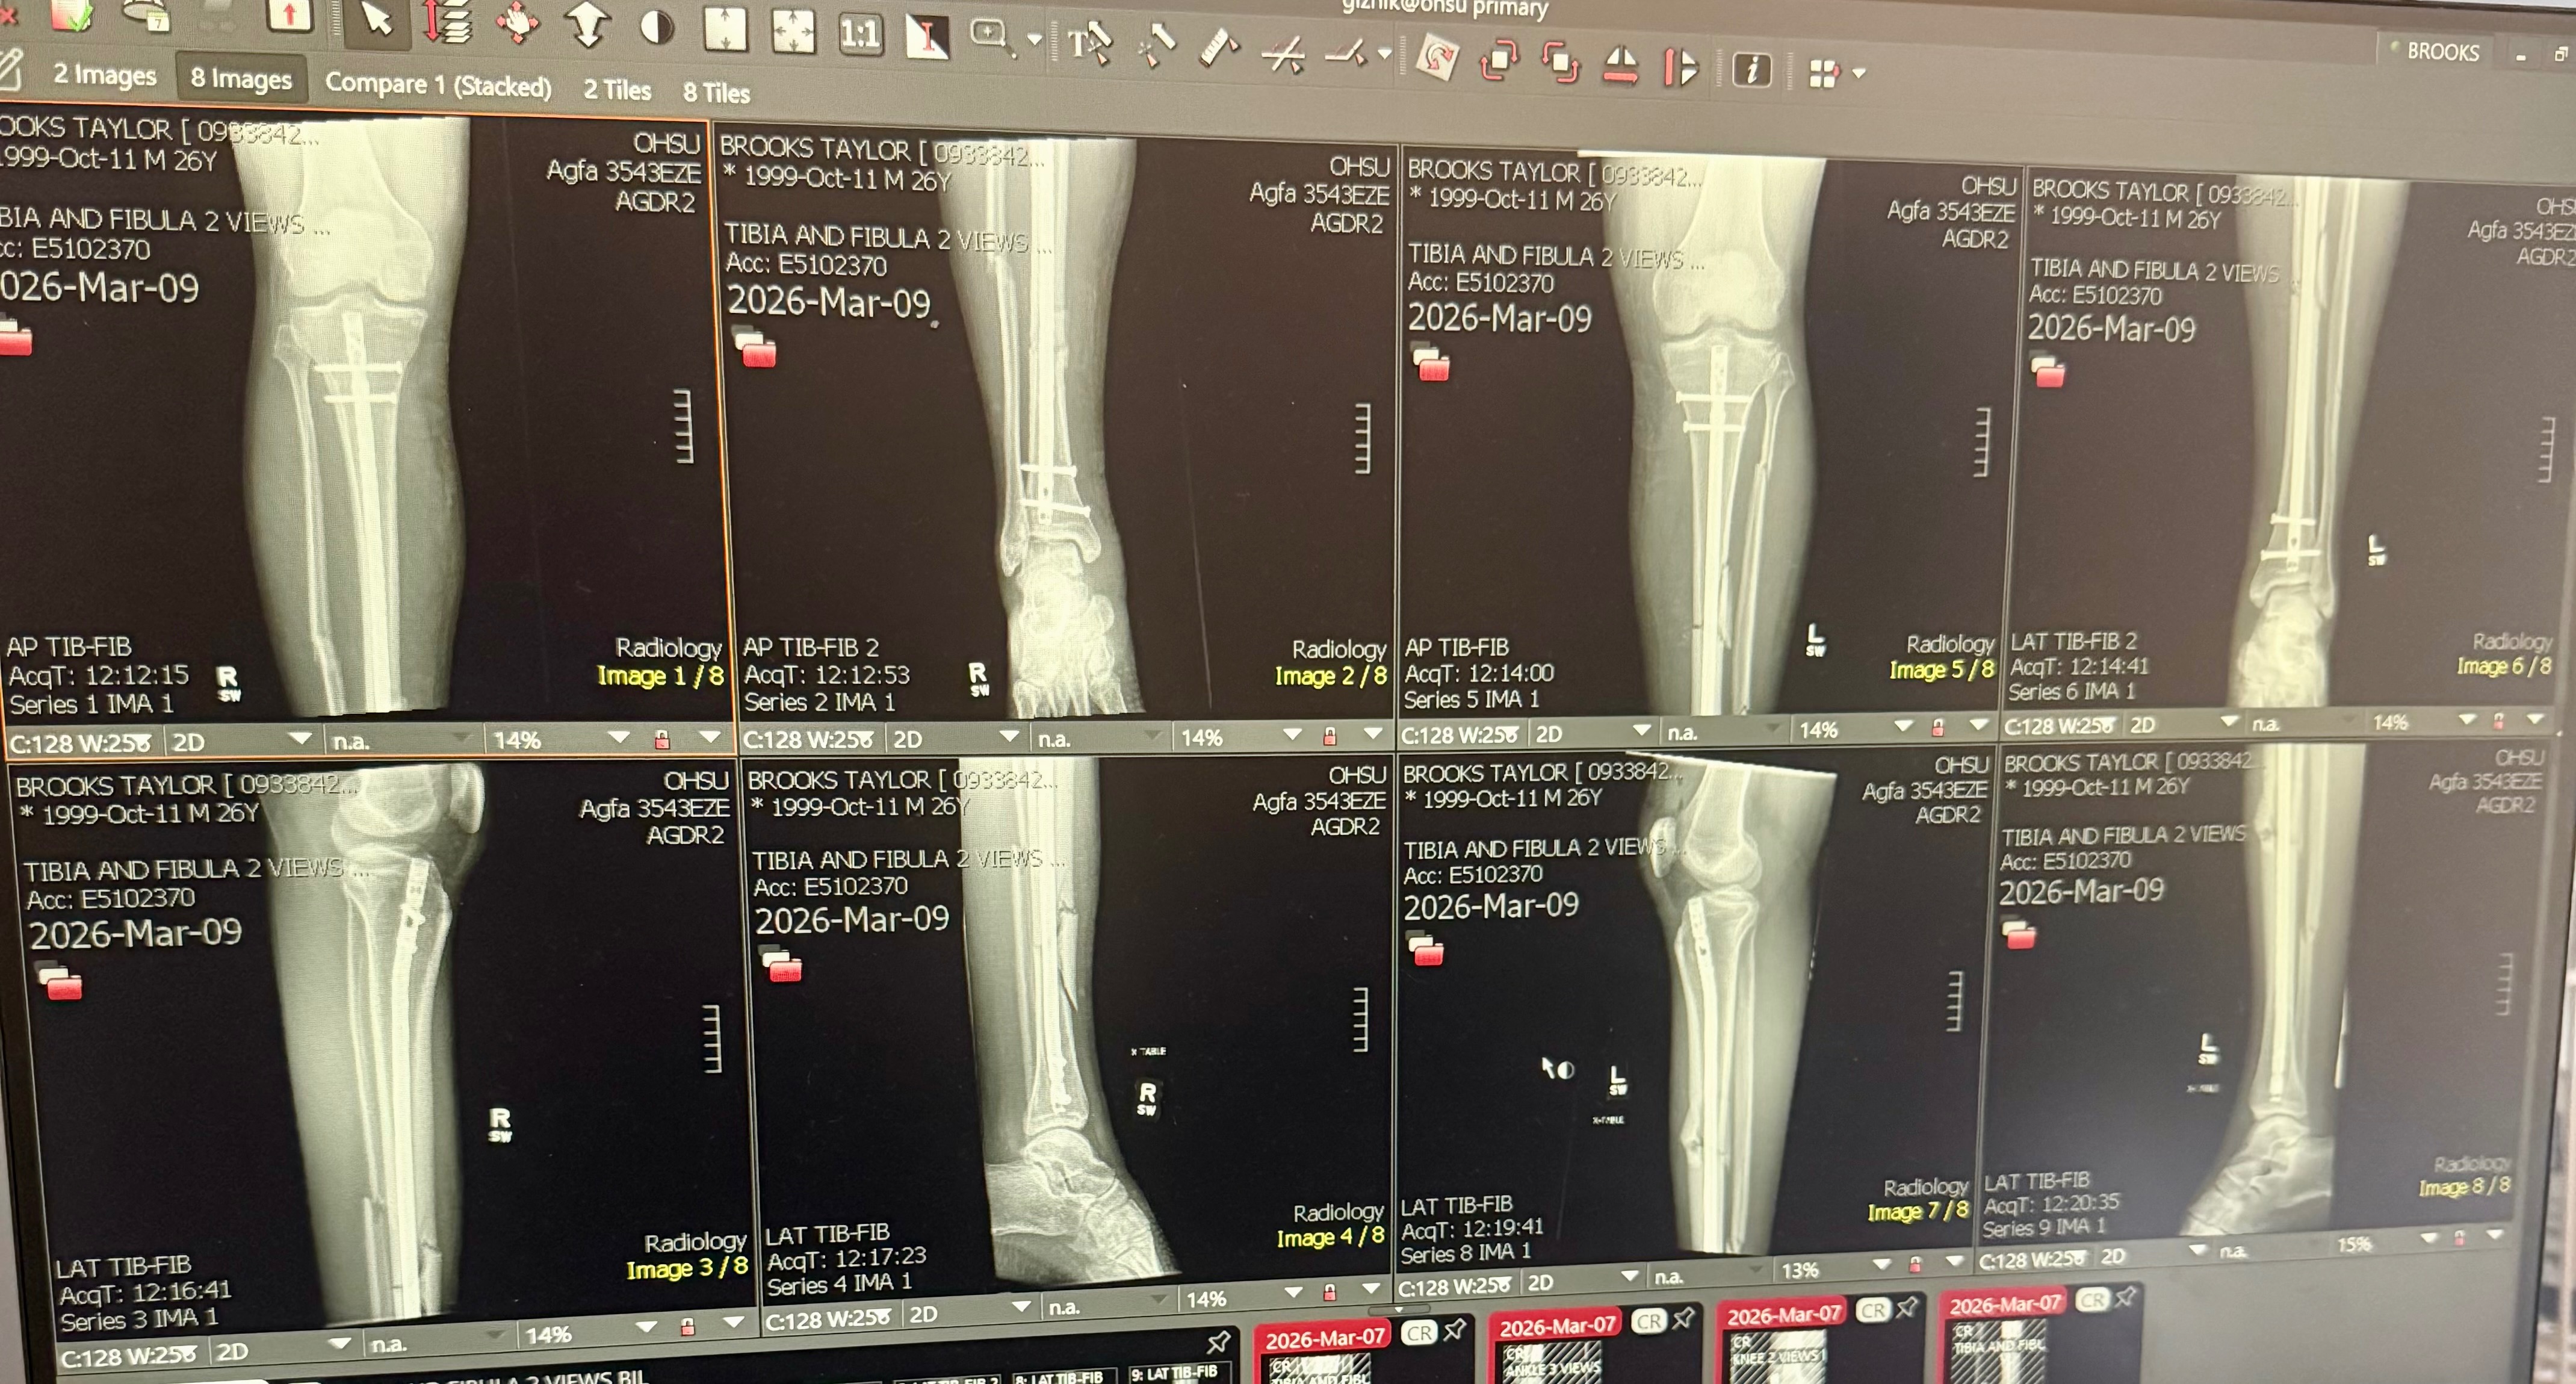

My daughter's boyfriend, Taylor, was in a tragic motorcycle accident, where a car pulled out in front of him, on his way to their gender reveal party on 3/7/26. Taylor was rushed by ambulance to OHSU, where they determined he had broken legs, which he had surgery for today, fractured ribs, collapsed lungs, and other injuries. Taylor is going to have a long road ahead of him in recovery with multiple doctor and physical therapy appointments. Samantha works hard, but she doesn't earn enough to make up for the lost income and extra expenses they will face in the future. I know they would appreciate prayers, shares, and any support you can offer.